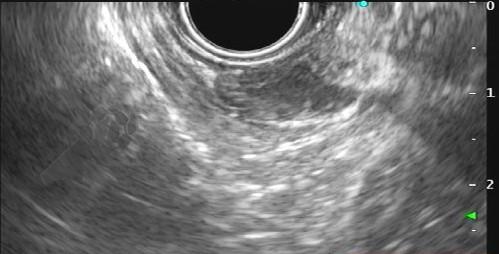

Imagem 1. Sinal da almofada (“pillow sign”) Fonte: Kim GH et al.16Imagem 2. Sinal do rolamento (“rolling sign”) Fonte: Kim GH et al.16Imagem 3. Sinal da tenda (“tenting sign”) Fonte: Kim GH et al.16Imagem 4. Ecoendoscopia demonstrando lesão com ecogenicidade hipoecoica, ecotextura homogênea, arredondada, limites bem definidos, contornos regulares, medindo 15 mm x 12 mm e inserida na camada muscular própria. A imagem permite demonstrar as camadas mucosa superficial, mucosa profunda, submucosa, muscular própria. Fonte: arquivos do Instituto do Câncer do Estado de São Paulo (ICESP/HCFMUSP).

Figuras 1 e 2. Imagem endoscópica em visão direta de lesão protrusa entre pequena curvatura e parede posterior de corpo gástrico proximal, revestida por mucosa com superfície regular, normocorada e íntegra. A imagem ecoendoscópica demonstra lesão com ecogenicidade hipoecoica, ecotextura homogênea, formato ovalado, sem características internas, sem vascularização ao doppler, limites precisos, contornos regulares, medindo aproximadamente 20 x 6 mm e inserida em camada muscular própria. Punções ecoguiadas foram realizadas com agulha FNB, sendo o anatomopatológico e imuno-histoquímica compatíveis com GIST gástrico. Fonte: arquivos do Instituto do Câncer do Estado de São Paulo (ICESP/HCFMUSP)Figuras 1 e 2. Imagem endoscópica em visão direta de lesão protrusa entre pequena curvatura e parede posterior de corpo gástrico proximal, revestida por mucosa com superfície regular, normocorada e íntegra. A imagem ecoendoscópica demonstra lesão com ecogenicidade hipoecoica, ecotextura homogênea, formato ovalado, sem características internas, sem vascularização ao doppler, limites precisos, contornos regulares, medindo aproximadamente 20 x 6 mm e inserida em camada muscular própria. Punções ecoguiadas foram realizadas com agulha FNB, sendo o anatomopatológico e imuno-histoquímica compatíveis com GIST gástrico. Fonte: arquivos do Instituto do Câncer do Estado de São Paulo (ICESP/HCFMUSP)Figuras 3 e 4. Imagem endoscópica em visão direta de abaulamento de parede em segunda porção duodenal distalmente à papila duodenal maior, revestida por mucosa com íntegra, de coloração amarelada e superfície regular. A ecoendoscopia demonstra lesão com ecogenicidade hiperecoica, ecotextura homogênea, formato arredondado, medindo cerca de 10 mm no maior eixo, com limites precisos, contornos regulares, medindo cerca de 10 mm no maior diâmetro e inserida em camada submucosa, sendo os achados endoscópicos e ecoendoscópicos compatíveis com lipoma.Figuras 3 e 4. Imagem endoscópica em visão direta de abaulamento de parede em segunda porção duodenal distalmente à papila duodenal maior, revestida por mucosa com íntegra, de coloração amarelada e superfície regular. A ecoendoscopia demonstra lesão com ecogenicidade hiperecoica, ecotextura homogênea, formato arredondado, medindo cerca de 10 mm no maior eixo, com limites precisos, contornos regulares, medindo cerca de 10 mm no maior diâmetro e inserida em camada submucosa, sendo os achados endoscópicos e ecoendoscópicos compatíveis com lipoma.Fig. 5. Imagem endoscópica em visão direta de lesão protrusa em parede anterior de antro gástrico proximal, revestida por mucosa normocorada, com superfície regular, sendo sugestiva de lesão subepitelial.Fig. 6. A ecoendoscopia evidencia lesão com ecogenicidade hipoecoica, ecotextura predominantemente homogênea, formato arredondado, limites precisos, bordos regulares, medindo aproximadamente 13,4 x 12 mm, sem focos hiperecoicos ou calcificações no interior e inserida na camada muscular própria. Punções ecoguiadas foram realizadas com agulha FNB, sendo anatomopatológico e imuno-histoquímica confirmando schwanomma gástrico.Fig. 7 e 8. Imagem de esofagogastroduodenoscopia demonstra lesão protrusa em papila duodenal maior revestida por mucosa enantemática e com superfície com três erosões recobertas por fibrina.Fig. 7 e 8. Imagem de esofagogastroduodenoscopia demonstra lesão protrusa em papila duodenal maior revestida por mucosa enantemática e com superfície com três erosões recobertas por fibrina.Fig. 9 e 10. Imagem à ecoendoscopia demonstra lesão com formato ovalado, ecogenicidade hipoecoica, ecotextura heterogênea, com contornos regulares, sem adenopatia adjacente, sem vascularização ao doppler, sem características internas, medindo cerca de 20 x 11 x 24 mm, inserida na camada submucosa, não havendo acometimento da muscular própria. Foram realizadas punções ecoguiadas com agulha FNA 22 gauge, sendo o anatomopatológico e imunohistoquímica compatíveis com tumor neuroendócrino de papila duodenal bem diferenciado grau 1.Fig. 9 e 10. Imagem à ecoendoscopia demonstra lesão com formato ovalado, ecogenicidade hipoecoica, ecotextura heterogênea, com contornos regulares, sem adenopatia adjacente, sem vascularização ao doppler, sem características internas, medindo cerca de 20 x 11 x 24 mm, inserida na camada submucosa, não havendo acometimento da muscular própria. Foram realizadas punções ecoguiadas com agulha FNA 22 gauge, sendo o anatomopatológico e imunohistoquímica compatíveis com tumor neuroendócrino de papila duodenal bem diferenciado grau 1.Fig. 11 e 12. Esofagogastroduodenoscopia demonstra abaulamento de parede anterior de corpo gástrico proximal, com mucosa normocorada, superfície regular com depressão central, sendo compatível com lesão subepitelialFig. 11 e 12. Esofagogastroduodenoscopia demonstra abaulamento de parede anterior de corpo gástrico proximal, com mucosa normocorada, superfície regular com depressão central, sendo compatível com lesão subepitelialFig. 13 e 14. Ecoendoscopia demonstrou formação com ecogenicidade hipoecoica, ecotextura homogênea, formato ovalado, limites bem definidos, contornos regulares, medindo aproximadamente 13 mm e inserida na camada submucosa. Lesão foi submetida a ressecção endoscópica transmural com dispositivo FTRD. A histopatologia e imunohistoquímica confirmaram TNE gástrico bem diferenciado grau 2.Fig. 13 e 14. Ecoendoscopia demonstrou formação com ecogenicidade hipoecoica, ecotextura homogênea, formato ovalado, limites bem definidos, contornos regulares, medindo aproximadamente 13 mm e inserida na camada submucosa. Lesão foi submetida a ressecção endoscópica transmural com dispositivo FTRD. A histopatologia e imunohistoquímica confirmaram TNE gástrico bem diferenciado grau 2.